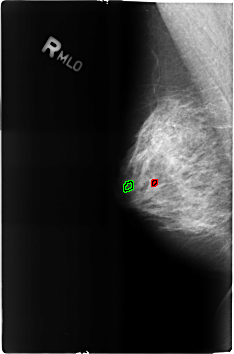

B_3205_1.RIGHT_MLO

FILE: B_3205_1.RIGHT_MLO.OVERLAY

TOTAL_ABNORMALITIES 2

ABNORMALITY 1

LESION_TYPE CALCIFICATION TYPE COARSE DISTRIBUTION N/A

ASSESSMENT 2

SUBTLETY 3

PATHOLOGY BENIGN_WITHOUT_CALLBACK

ABNORMALITY 2

LESION_TYPE CALCIFICATION TYPE LUCENT_CENTER DISTRIBUTION N/A